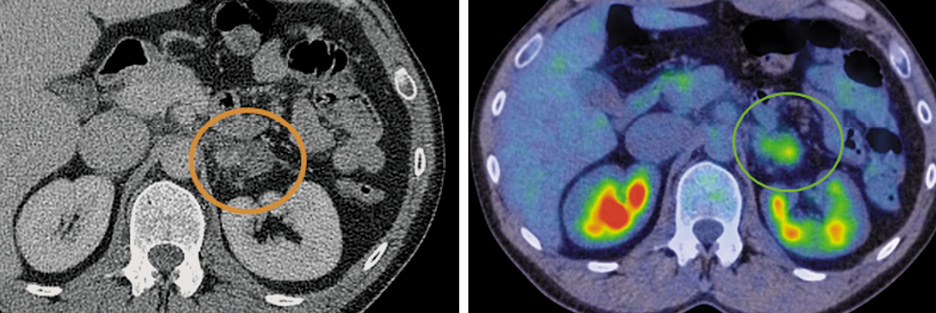

В левом надпочечнике также обнаружено объемное образование кистозно-солидной структуры с гетерогенным контрастным усилением размером 25×35 мм с патологическим накоплением 18-ФДГ, SUVmax 3,44 (рис. 3).

Рис. 3. Больной С., 43 года. На аксиальной КТ- и совмещенной ПЭТ/КТ-проекциях в левом надпочечнике определяется образование размером 25×35 мм, с повышенной фиксацией радиофармпрепарата, SUVmax 3,44.